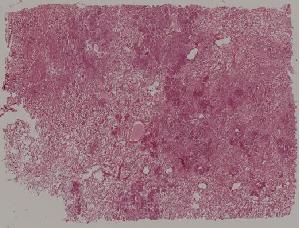

57. Carcinoma of the lung

59. Chronic atrophic gastritis

60. Gastric ulcer

61. Gastric adenocarcinoma(Mucinous adenocarcinoma of the stamoch)